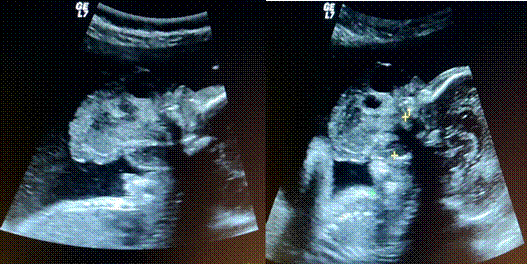

Paciente de 17 años de edad, primigesta, quien acudió a la Unidad de Perinatología Dr. “Freddy Guevara Zuloaga” del Hospital Universitario de Caracas para evaluación ecográfica del segundo trimestre, referida de la consulta de genética. Negó antecedentes personales y familiares de importancia, exposición a agentes teratógenos o lazos de consanguinidad con la pareja; el paneo serológico de infecciones resultó negativo. En exploración ecográfica del embarazo de 24 semanas y 2 días según la ecografía del primer trimestre, se encontró un feto único en situación transversa, dorso posterior, actividad cardíaca presente. Se evidenció una imagen ecomixta que impresionaba provenir de la parte posterior de la lengua, a través de la cavidad oral; que imposibilitaba el cierre de la misma; con medidas 69 x 45 mm. doppler color positivo. El maxilar superior impresionó indemne. No se observaron otras anomalías estructurales mayores. Se reportó como signos ecográficos sugestivos de patología fetal del macizo facial: epignatus (Figura 1 y 2).

Figura 1: Corte sagital de cara fetal. Imagen ecomixta de bordes irregulares que proviene de la parte posterior de la lengua, de predominio sólido en la parte media de la cara; que protruye a través de la cavidad oral que mide 69 x 45 mm